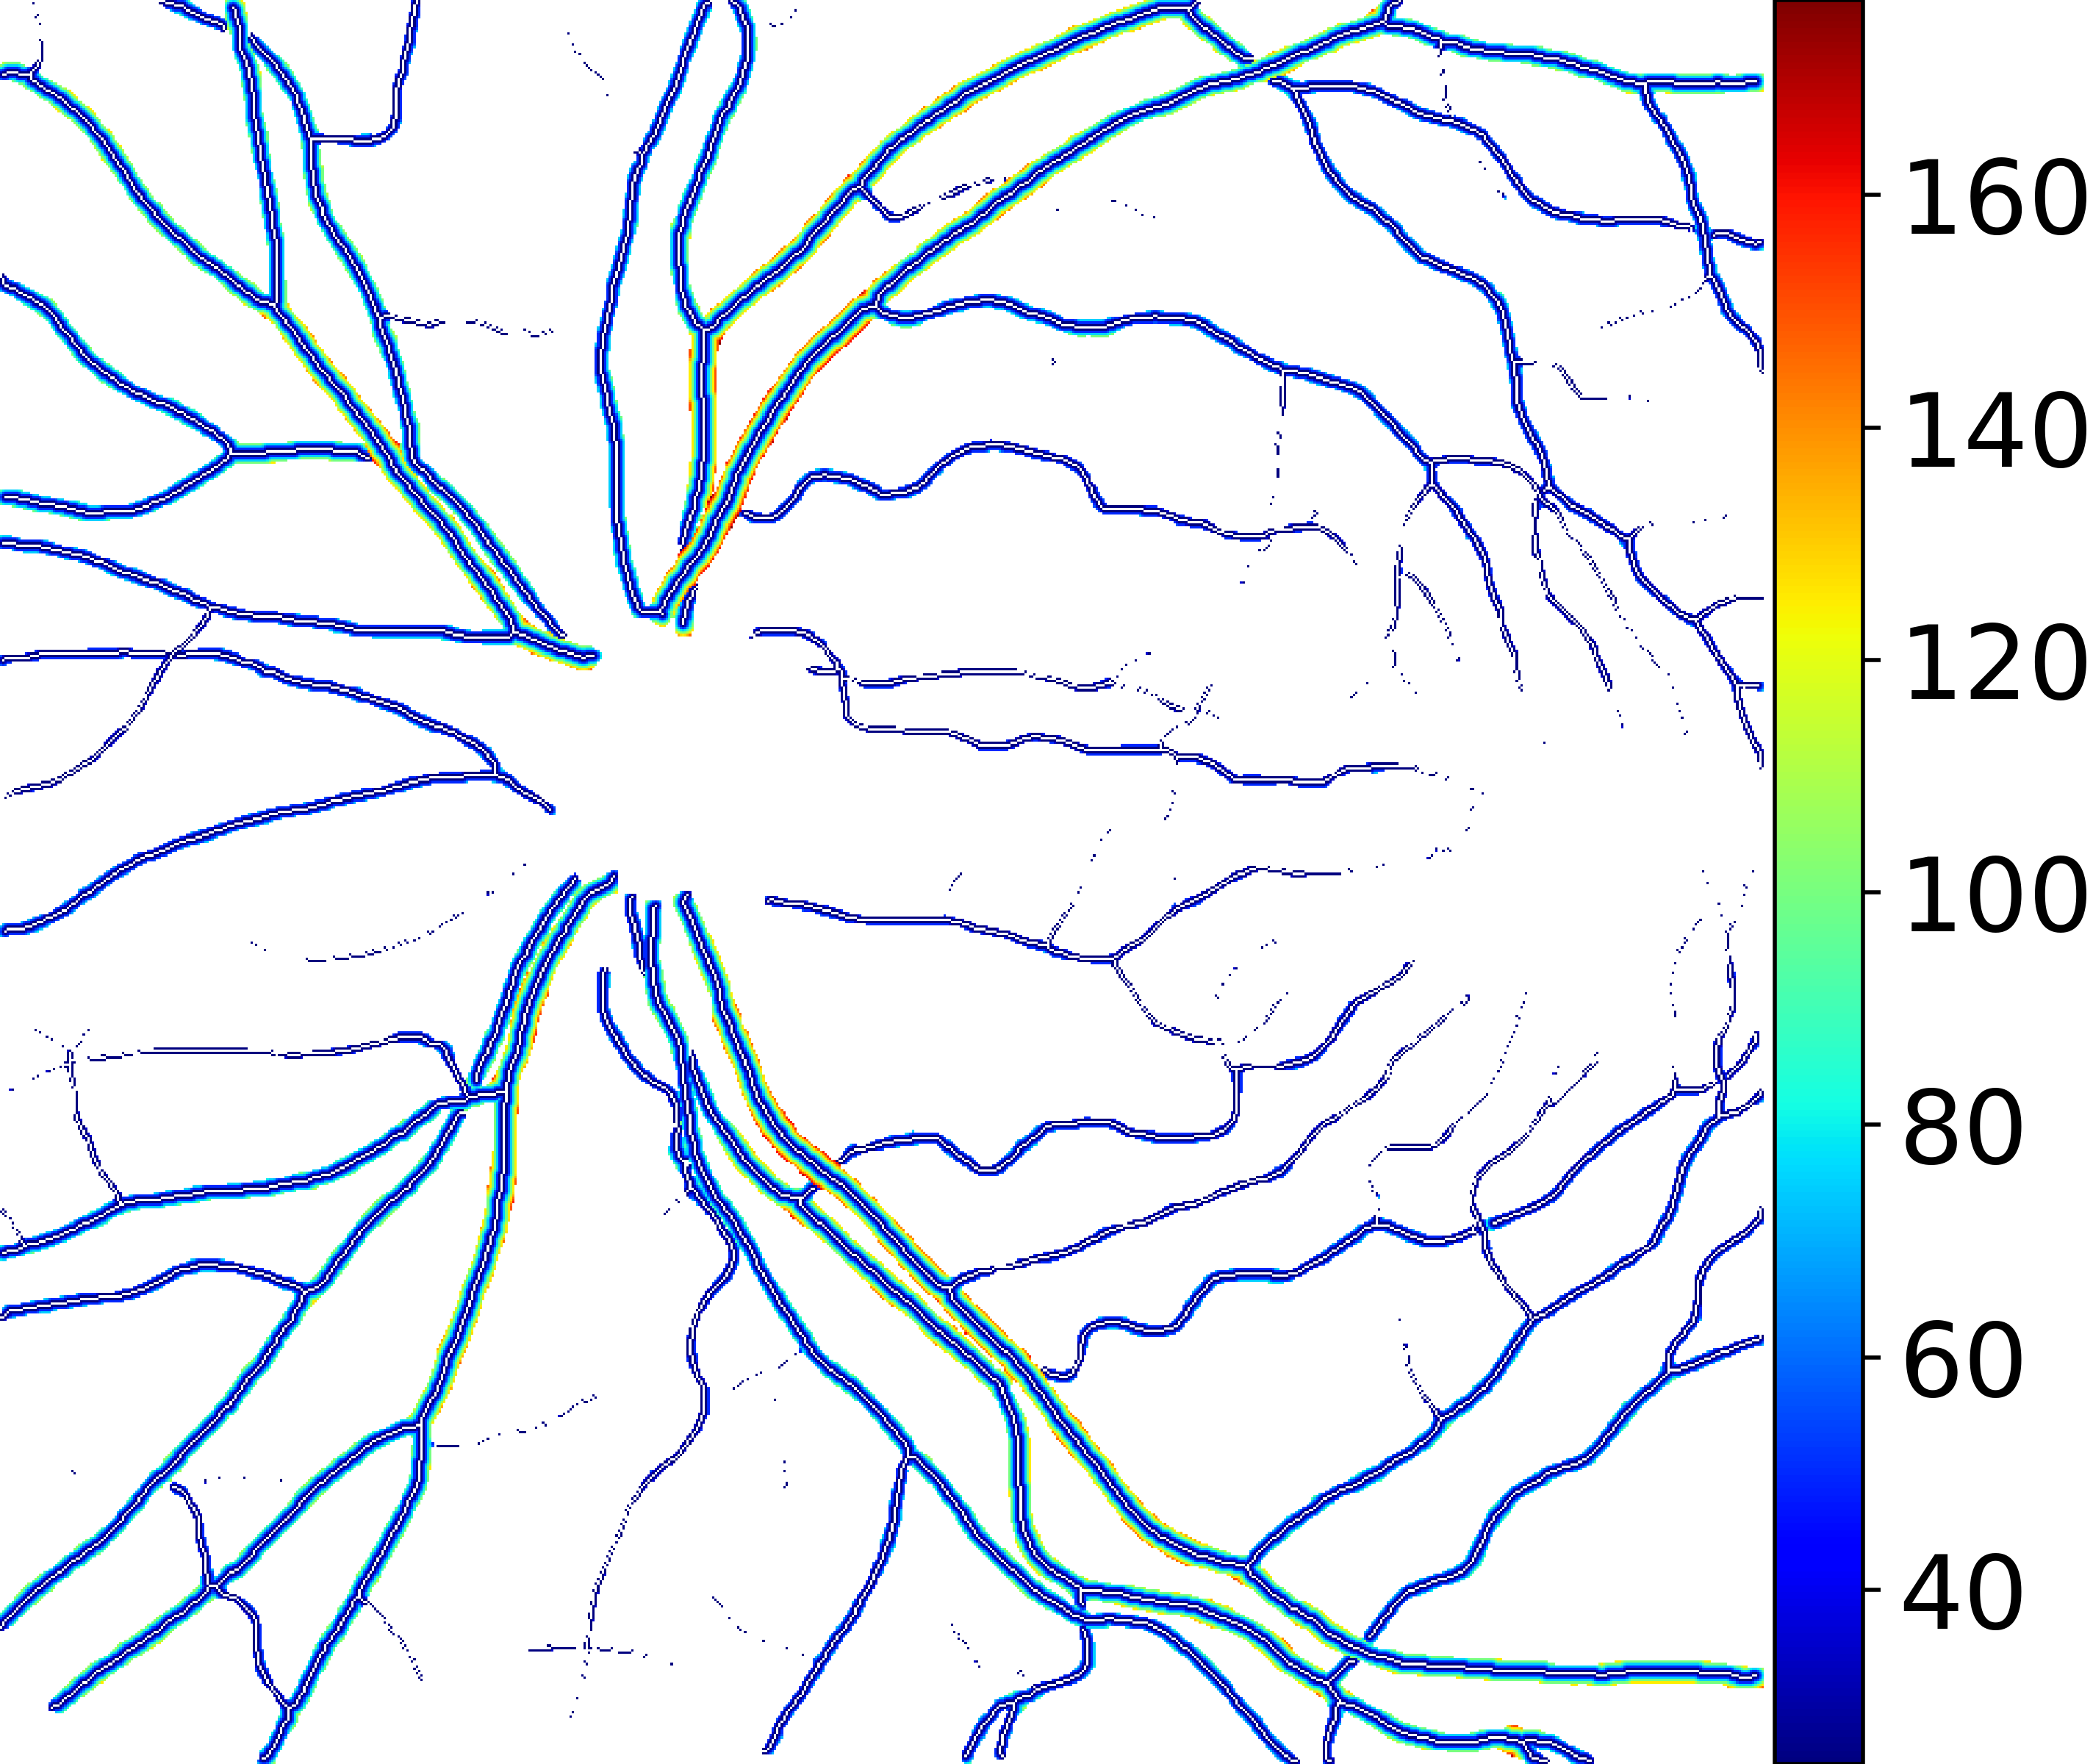

IV-C Vessel Width Estimation

From the segmentation predicted by the SegRAVIR network, our model measures the diameter of the arteries and veins. To this end, the segmentation probability map is first thresholded, using a constant value of 0.5, to obtain the medial curves of the vessels by iteratively identifying and removing border pixels while maintaining vessel connectivity, in an approach similar to the thinning algorithm presented by Zhang et al. [49]. Then, the distance transform of the medial curve mask is multiplied with the segmentation mask in a pixel-wise manner. The result is the diameter distance map with respect to the medial curves of the segmented vessels.

VI-B Vessel Width Estimation

Table VI presents a quantitative comparison of the measured diameters using the segmentation outputs of SegRAVIR and competing approaches. Using the pixel-wise annotated masks, the reference average diameter of the arteries and veins in the test set of the RAVIR dataset were measured as and , respectively. According to our analysis, SegRAVIR can accurately measure the diameter of the vessels and it achieves the smallest MAPE among the competing approaches. Specifically, in comparison to CE-Net, Iter-Net, and DU-Net, respectively, SegRAVIR is on average , and more accurate in terms of MAPE for the measured diameter of arteries and , and in terms of MAPE for the measured diameter of veins. Fig. 6 presents qualitative comparisons of reference and SegRAVIR estimated diameter maps.

(a) (b) (c)